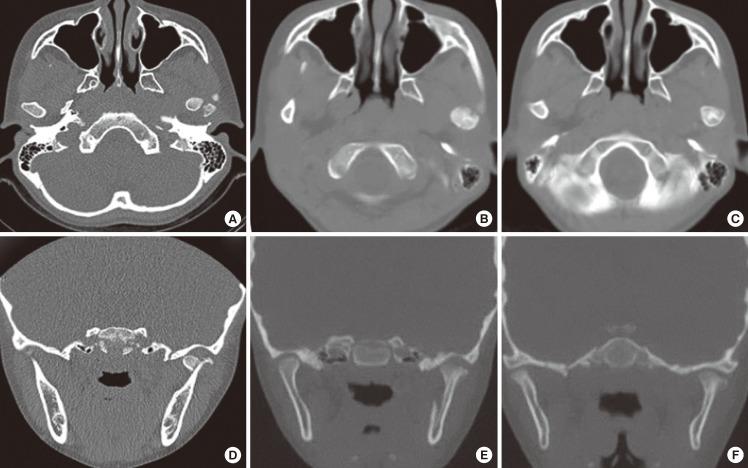

在治疗下颌髁突骨折时,可采用闭合复位的保守治疗或切开复位的手术治疗。下颌髁突骨折的处理在口腔颌面创伤领域仍是一个持续存在争议的问题。对于每种类型的髁突骨折,必须考虑牙齿的存在情况、骨折高度、患者适应性、患者咀嚼系统、咬合功能紊乱以及下颌偏斜等因素来选择治疗方法。过去,主要采用在恢复期行颌间固定后进行闭合复位并辅以积极物理治疗的方法,但近年来,采用坚固内固定的髁突骨折切开治疗更为常见。本综述的目的是评估决定髁突骨折开放或闭合治疗方法选择的主要变量,确定其适应证、优点和缺点,并评价目前关于下颌髁突骨折治疗中所用干预措施有效性的证据。

https://cdn.ncbi.nlm.nih.gov/pmc/blobs/e210/3408273/c2342bf177f6/aps-39-301-g005.jpg